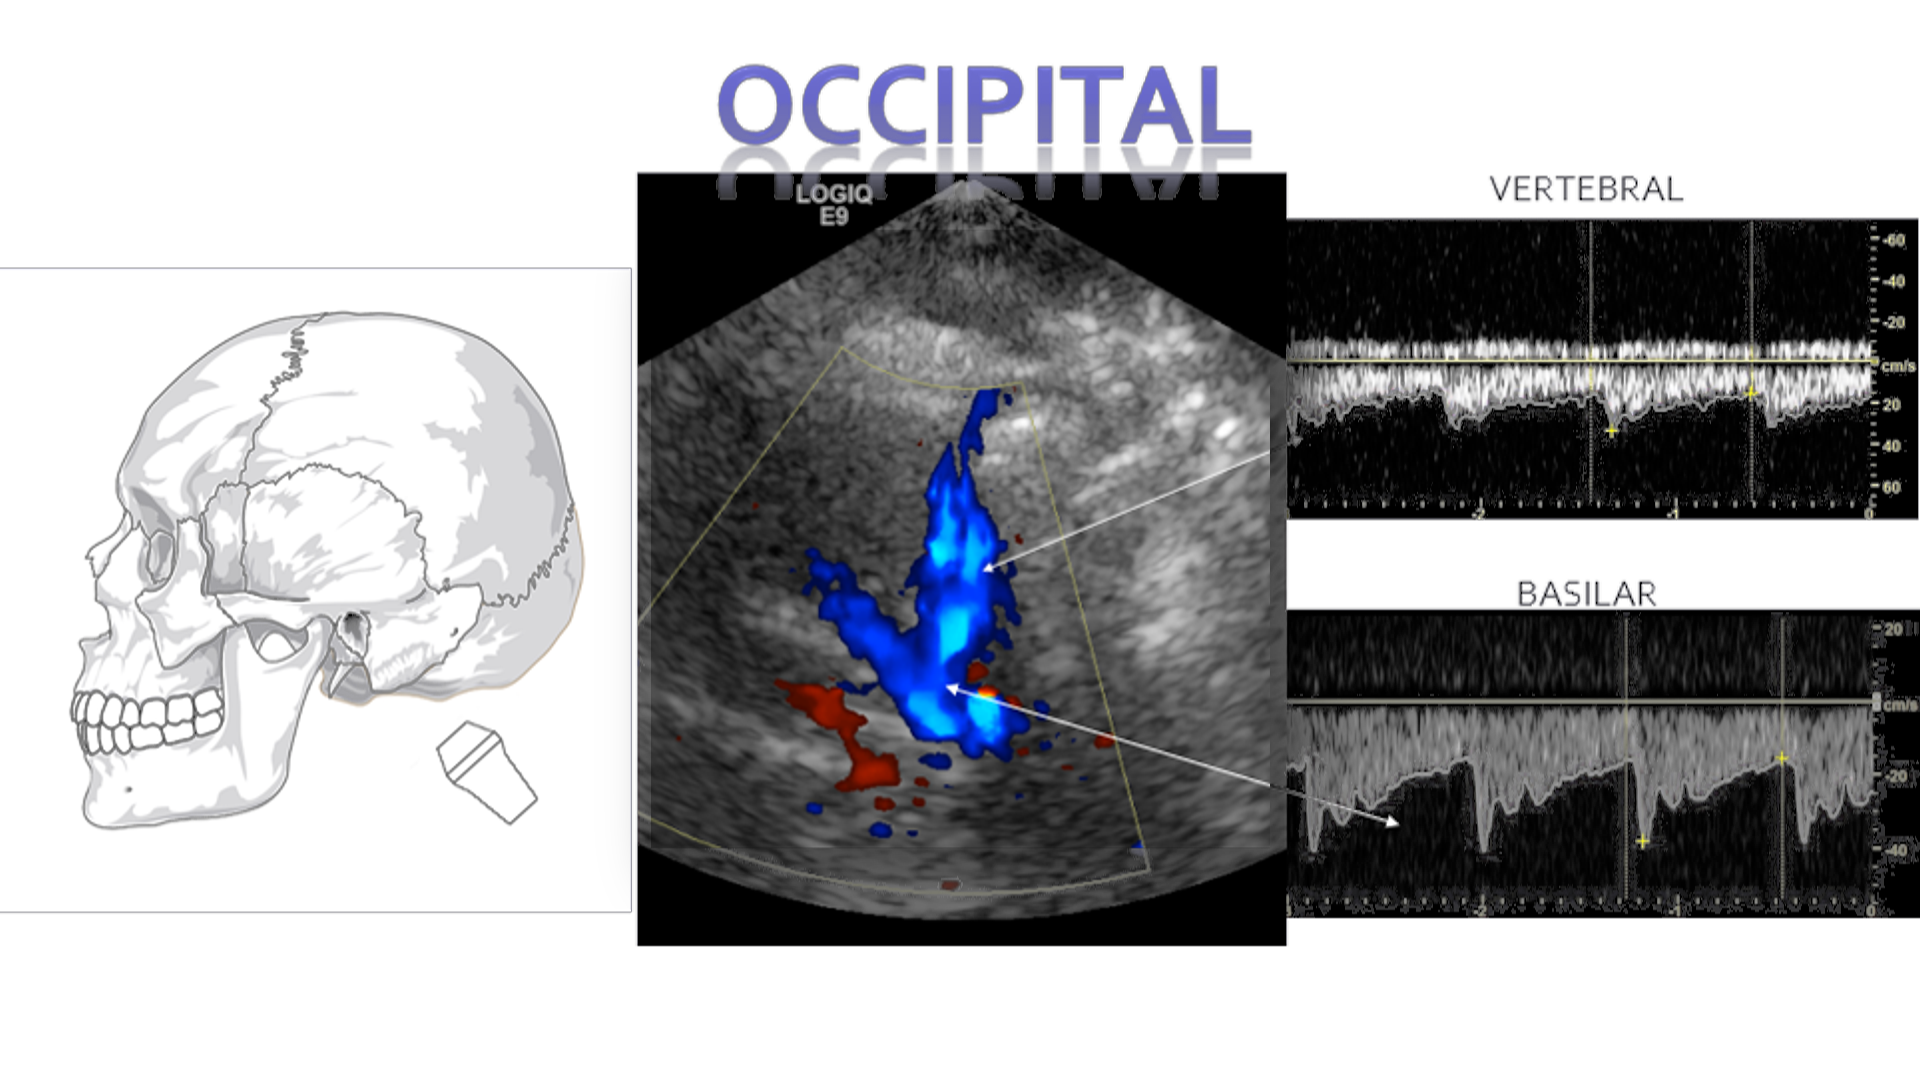

Occipital/Trans-Foraminal

In the occipital or trans-forminal window you will encounter the bilateral Vertebral arteries and singular Basilar artery. The flow will be below baseline for both. These arteries join to form the posterior cerebral arteries.